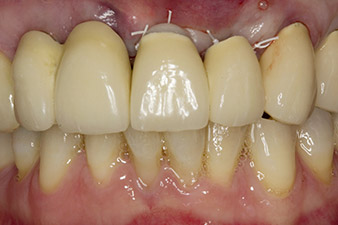

Nach primärer Abheilung werden die Weichgewebe mithilfe der basal unterfütterten Brücke ausgeformt. Zwei Monate später erfolgt die Freilegung mit einem leicht palatinal gelegten Kieferkammschnitt (Abb. 2).

Pilotbohrung mit dem neuen Implantmed und dem Winkelstück WS-56 L

Abb. 2: Zwei Monate später erfolgt die Pilotbohrung mit dem neuen Implantmed und dem Winkelstück WS-56 L (Programm P1, Übersetzung 1:1). Die Kühlung erfolgt über das links positionierte Sprayrohr (für Rechtshänder).